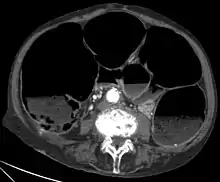

CT-Scan showing a Cross-section of the abdomen of an elderly lady with an IPO. - CT scans